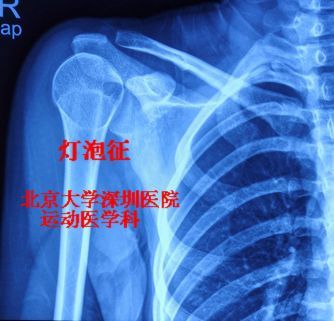

在肩关节正位片,或者是肩胛骨正位片上,可以看到肱骨头旋转脱位后骨小

图片尺寸334x321